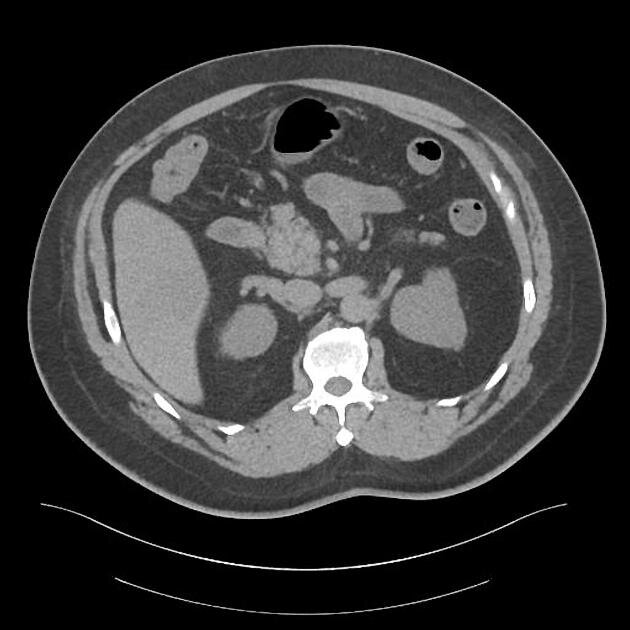

3) КТ брюшной полости

КТ брюшной полости